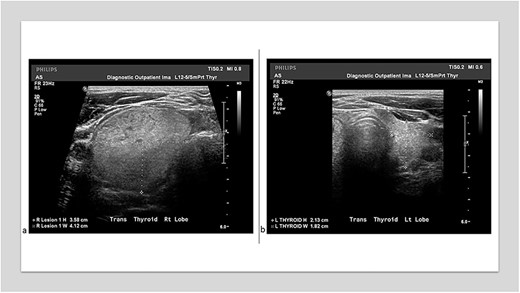

Neck ultrasound demonstrated an enlarged right-sided with a nodule (measuring 3.58 × 4.12 cm) and two left-sided nodules measuring 1.1 and 1.4 cm in size (Fig. 1a and b). The ultrasound also showed a 1 cm nodule inferior to the left lobe, suspicious of a parathyroid adenoma or enlarged lymph node. CT chest revealed multiple nodules in the left pulmonary parenchyma (Fig. 2). Flexible laryngoscopy revealed normal bilateral vocal cord movement but severe inflammation and swelling of the larynx. Subsequent FNA of both the right and left thyroid nodules showed benign results.

(a) Thyroid ultrasound showed an isoechoic 3.58 × 4.12 cm3 nodule in the right lobe. (b) A thyroid ultrasound showed a left lobe 2.13 × 1.82 cm3.